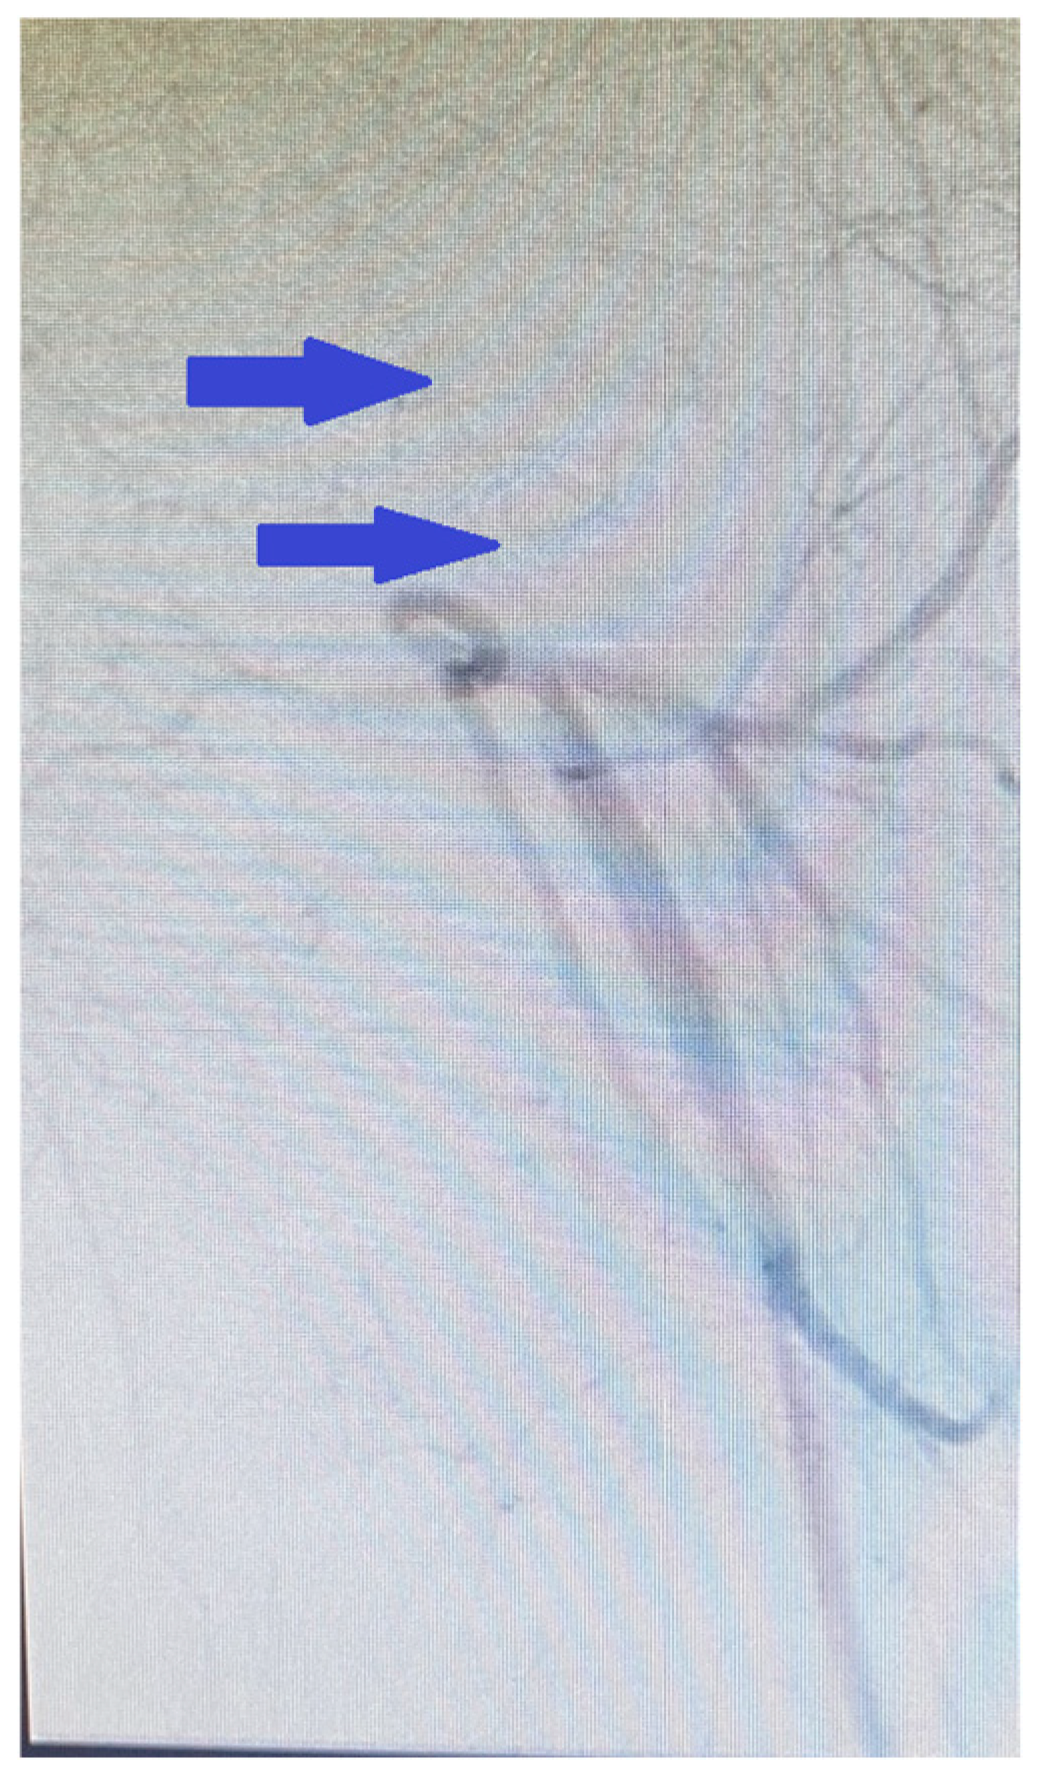

These findings supported deep vein thrombosis complicated by pulmonary embolism. The diagnosis was confirmed using non-contrast computed tomography (CT) and CT pulmonary angiography with reconstruction. Imaging studies revealed that the pulmonary trunk had homogenous contrast enhancement, which was at the upper limit of normal dimensions (<29 mm). The right and left pulmonary arteries exhibited an extensive saddle-shaped filling defect (Figure 4A) with intraluminal occlusions bilaterally, including the interlobar and segmental branches (Figure 4B).

Figure 4. (A,B) CT pulmonary angiography with 3D reconstruction imaging the right and left pulmonary arteries exhibiting an extensive saddle-shaped filling defect with intraluminal occlusions bilaterally, including the interlobar and segmental branches (yellow arrows).